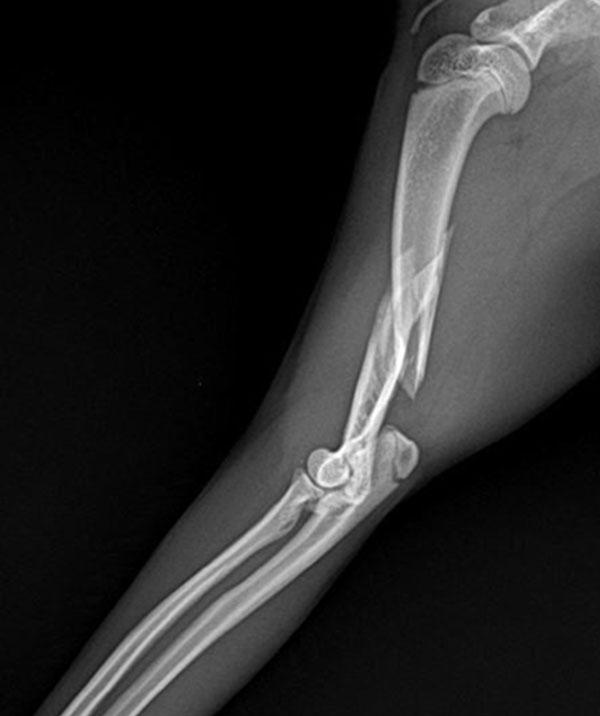

정형외과는 뼈, 관절, 인대, 힘줄, 근육 등 근골격계와 관련된 질환을 예방, 진단, 치료하는 의학의 한 분야입니다. 고양이를 포함한 동물들의 근골격계 질환을 다루는 정형외과는 골절, 탈구, 관절염, 슬개골 탈구 등 다양한 질환을 치료하고, 수술적 치료뿐만 아니라 보존적 치료와 재활 치료도 함께 제공합니다.